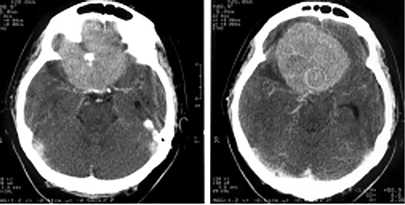

Менингиомы ольфакторной ямки (рис. 3)

Рисунок 3. Менингиома ольфакторной ямки (КТ с контрастным усилением)

Они могут располагаться симметрично относительно средней линии или распространяться преимущественно в одну сторону, часто сочетаются с гиперостозом. Эти новообразования характеризуются длительным бессимптомным периодом. В некоторых случаях опухоли гигантских размеров проявляются лишь умеренной лобной психопатологической симптоматикой, нарушениями обоняния и застойными дисками зрительных нервов. Опухоль может распространяться экстракраниально в решетчатую пазуху, медиальные отделы глазниц, носоглотку.